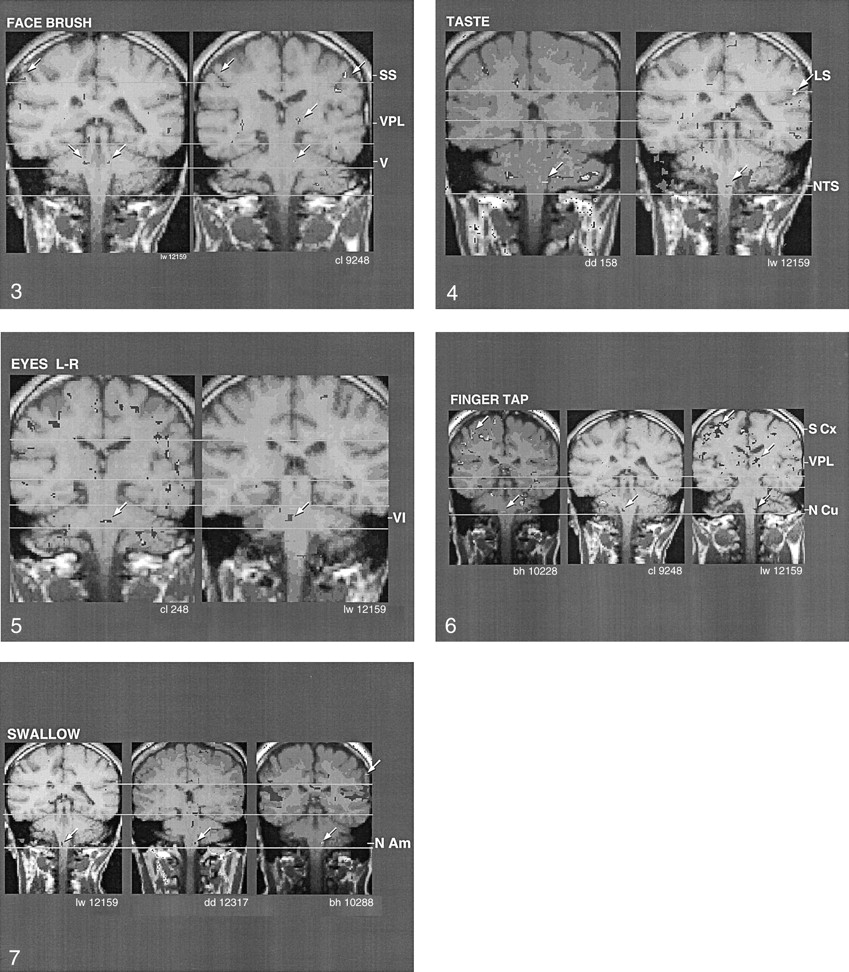

As shown in Figure 3, consistency was observed between the regions of BOLD activation in the pons and somatosensory cortex in two individuals, in response to brushing of the face. In addition, note the region of BOLD activation in the somatosensory thalamus (ie, VPL) in one of the individuals (right image). The triple activation in response to brushing the face was consistent with facial stimulation–induced activation of main trigeminal nucleus of the pons (CN V), VPL of the thalamus, and homuncular facial region of the somatosensory cortex. A probable clinical correlate of these findings of a response to face brushing is the report of cutaneous anesthesia in the maxilla and other facial regions in two cases of a relatively circumscribed lesion in this brain region (26). For bilaterally activated motor or sensory tasks, we often observed only unilateral BOLD activation; this finding was consistent with that of previous reports (19, 20).

Coronal images show the similarity of activation (arrows) produced by brushing the face, which corresponds to the region of the trigeminal main sensory nucleus (V), in two individuals. Note activation of nucleus ventralis posteromedialis (VPL) in one of the individuals and of somatosensory cortex (SS) in both individuals.

Figure 4 shows interindividual consistency in BOLD activation in the region of the superior level of the NTS in the medulla oblongata, in correlation with the taste stimulus. Note the activation of the sensory cortex (right image) at the level of the lateral sulcus, which closely corresponded to the homuncular tongue region.

Figure 5 shows interindividual reliability in the region of BOLD activation in correlation with left-to-right eye movement. The pontine location of activation near the midline was consistent with activation of the abducens nucleus (CN VI). Figure 6 shows that the region of BOLD activation in relation to finger tapping was consistent among three individuals. This finding corresponded to the region of the nucleus cuneatus, which receives afferent activity from the hands. In addition, the region of BOLD activation in the sensory cortex corresponded to the homuncular region for the fingers (note that this region of activation was superior to that in the face in Figure 2). Furthermore, in one subject (right image), BOLD activation was evident in the somatosensory thalamus (region of the nucleus VPL); this finding was consistent with afferent activation from the fingers.

Figure 7 shows the BOLD activation pattern that was correlated with dry swallowing (ie, Mendelsohn maneuver). This movement required activation of the nucleus ambiguus of the medulla oblongata. The images show that the region of the nucleus ambiguus was consistently activated in three individuals during the performance of this task. Note the activation at the inferolateral aspect of the motor cortex just superior to the lateral sulcus (upper arrow, right image), which corresponded to the homuncular pharyngeal region.